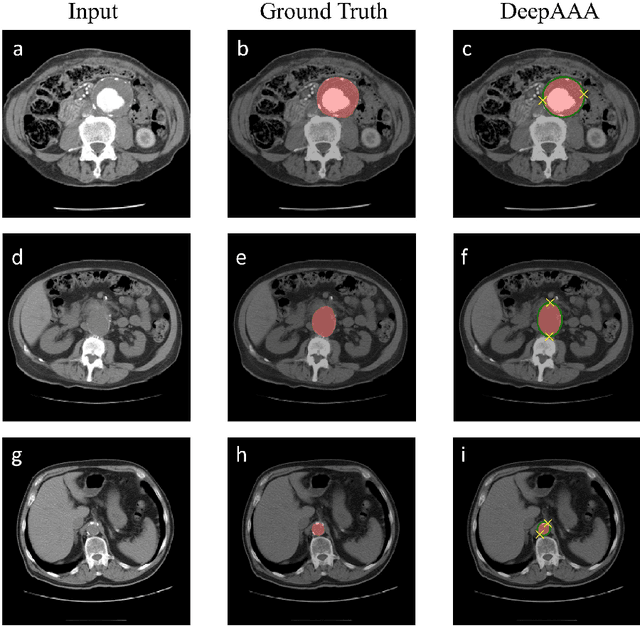

Abstract:We propose a deep learning-based technique for detection and quantification of abdominal aortic aneurysms (AAAs). The condition, which leads to more than 10,000 deaths per year in the United States, is asymptomatic, often detected incidentally, and often missed by radiologists. Our model architecture is a modified 3D U-Net combined with ellipse fitting that performs aorta segmentation and AAA detection. The study uses 321 abdominal-pelvic CT examinations performed by Massachusetts General Hospital Department of Radiology for training and validation. The model is then further tested for generalizability on a separate set of 57 examinations with differing patient demographics and acquisition characteristics than the original dataset. DeepAAA achieves high performance on both sets of data (sensitivity/specificity 0.91/0.95 and 0.85 / 1.0 respectively), on contrast and non-contrast CT scans and works with image volumes with varying numbers of images. We find that DeepAAA exceeds literature-reported performance of radiologists on incidental AAA detection. It is expected that the model can serve as an effective background detector in routine CT examinations to prevent incidental AAAs from being missed.